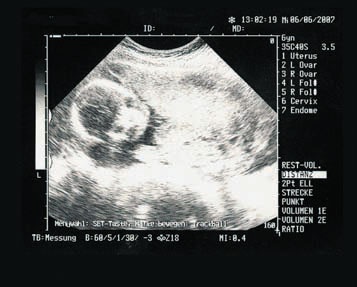

Иллюстрация к книге — От нуля до букваря [i_024.jpg]

Взятие околоплодной жидкости или биопсия оболочек плода (для анализа ворсин хориона) производится под контролем ультразвукового исследования, что практически исключает повреждение плода. Так что не стоит бояться этого обследования, тем более что его результаты имеют большую ценность для дальнейшего течения беременности и благополучия семьи.